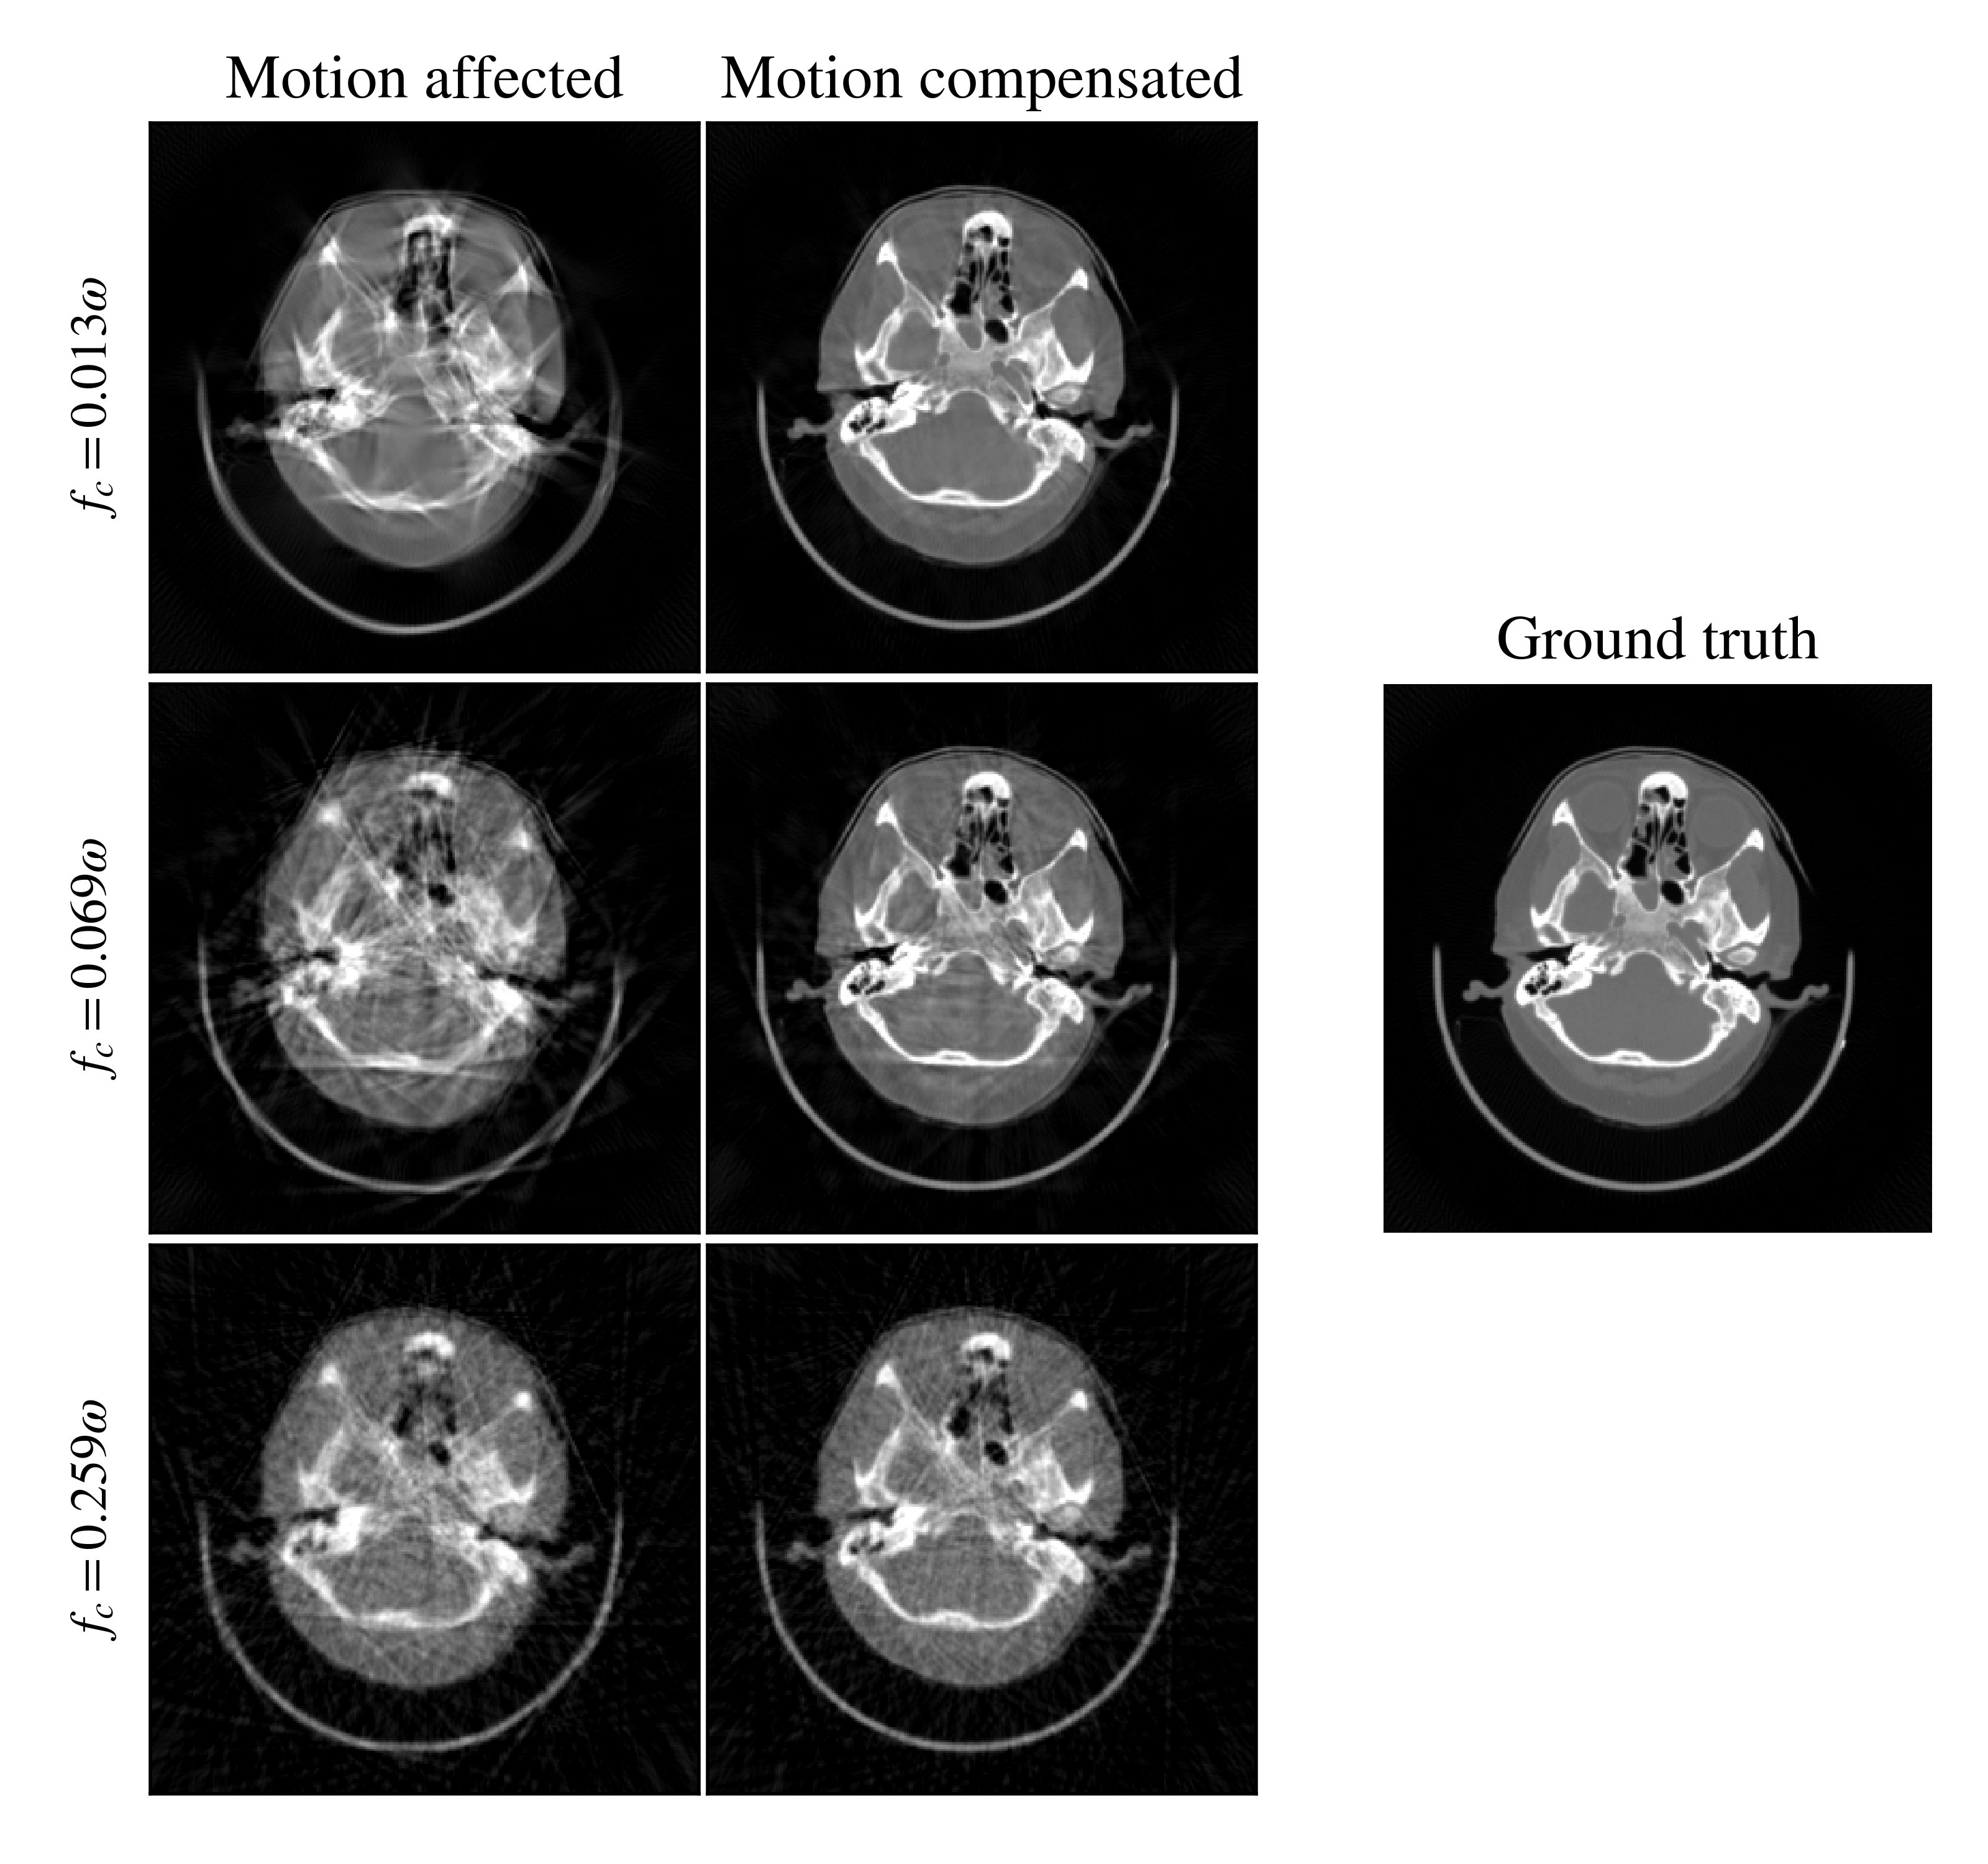

Refer to caption

Figure 4: Reconstruction results for an axial slice of one example scan from three different cutoff frequencies for the perturbing motion pattern and a spline with 100 nodes for the estimated signal. The ground truth is identical for all three cases. Motion-compensated results appear best for the lowest frequency and worst for the highest frequency.

Fig. 4 shows reconstructed results obtained from the same scan but with three different cutoff frequencies for the perturbing motion pattern. Looking at the motion-affected slices, we see that the frequency of the motion pattern has a strong influence on the appearance of the motion artifacts. Low frequencies lead to distortions of the shapes and misaligned edges, but some areas are still mostly homogeneous. High frequencies, in contrast, result in overall blurring of the reconstructed image and pronounced streak artifacts which affect all regions of the image. The motion-compensated results obtained with 100 nodes recover these artifacts well for the two lower frequencies and yield reconstructed images which resemble the ground truth closely. However, for fc=0.069ωsubscript𝑓𝑐0.069𝜔f_{c}=0.069\omega some inhomogeneities remain especially for soft tissue areas. The highest frequency in the figure fc=0.259ωsubscript𝑓𝑐0.259𝜔f_{c}=0.259\omega is above the critical frequency for 100 nodes according to the Nyquist-Shannon theorem. Therefore, the motion-compensated result sharpens the bone structures to some extent, but can not recover the blur and streaking artifacts caused by the high-frequency motion components.